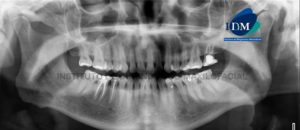

Paciente masculino de 7 años de edad, es referido al Instituto de Diagnóstico Maxilofacial – IDM para examen tomográfico por presentar alteración morfológica en la